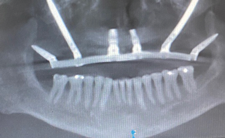

Treatment options for full-arch restorations include the placement of conventional implants in the anterior region accompanied by single zygomatic implants in the posterior left and right (Figure 1),48 the classic "quad zygoma" concept with four zygomatic implants in position (Figure 2),19,49 and the pterygoid fixated arch stabilization technique, which combines two anterior conventional implants, two zygomatic implants, and two pterygoid implants (Figure 3).50 Treatment plans can now be customized to optimize the implant positions based on each patient's anatomy and needs.

(3.) Radiograph of the pterygoid fixated arch stabilization technique, which includes two pterygoid, two zygomatic, and two conventional implants.

Figure 3